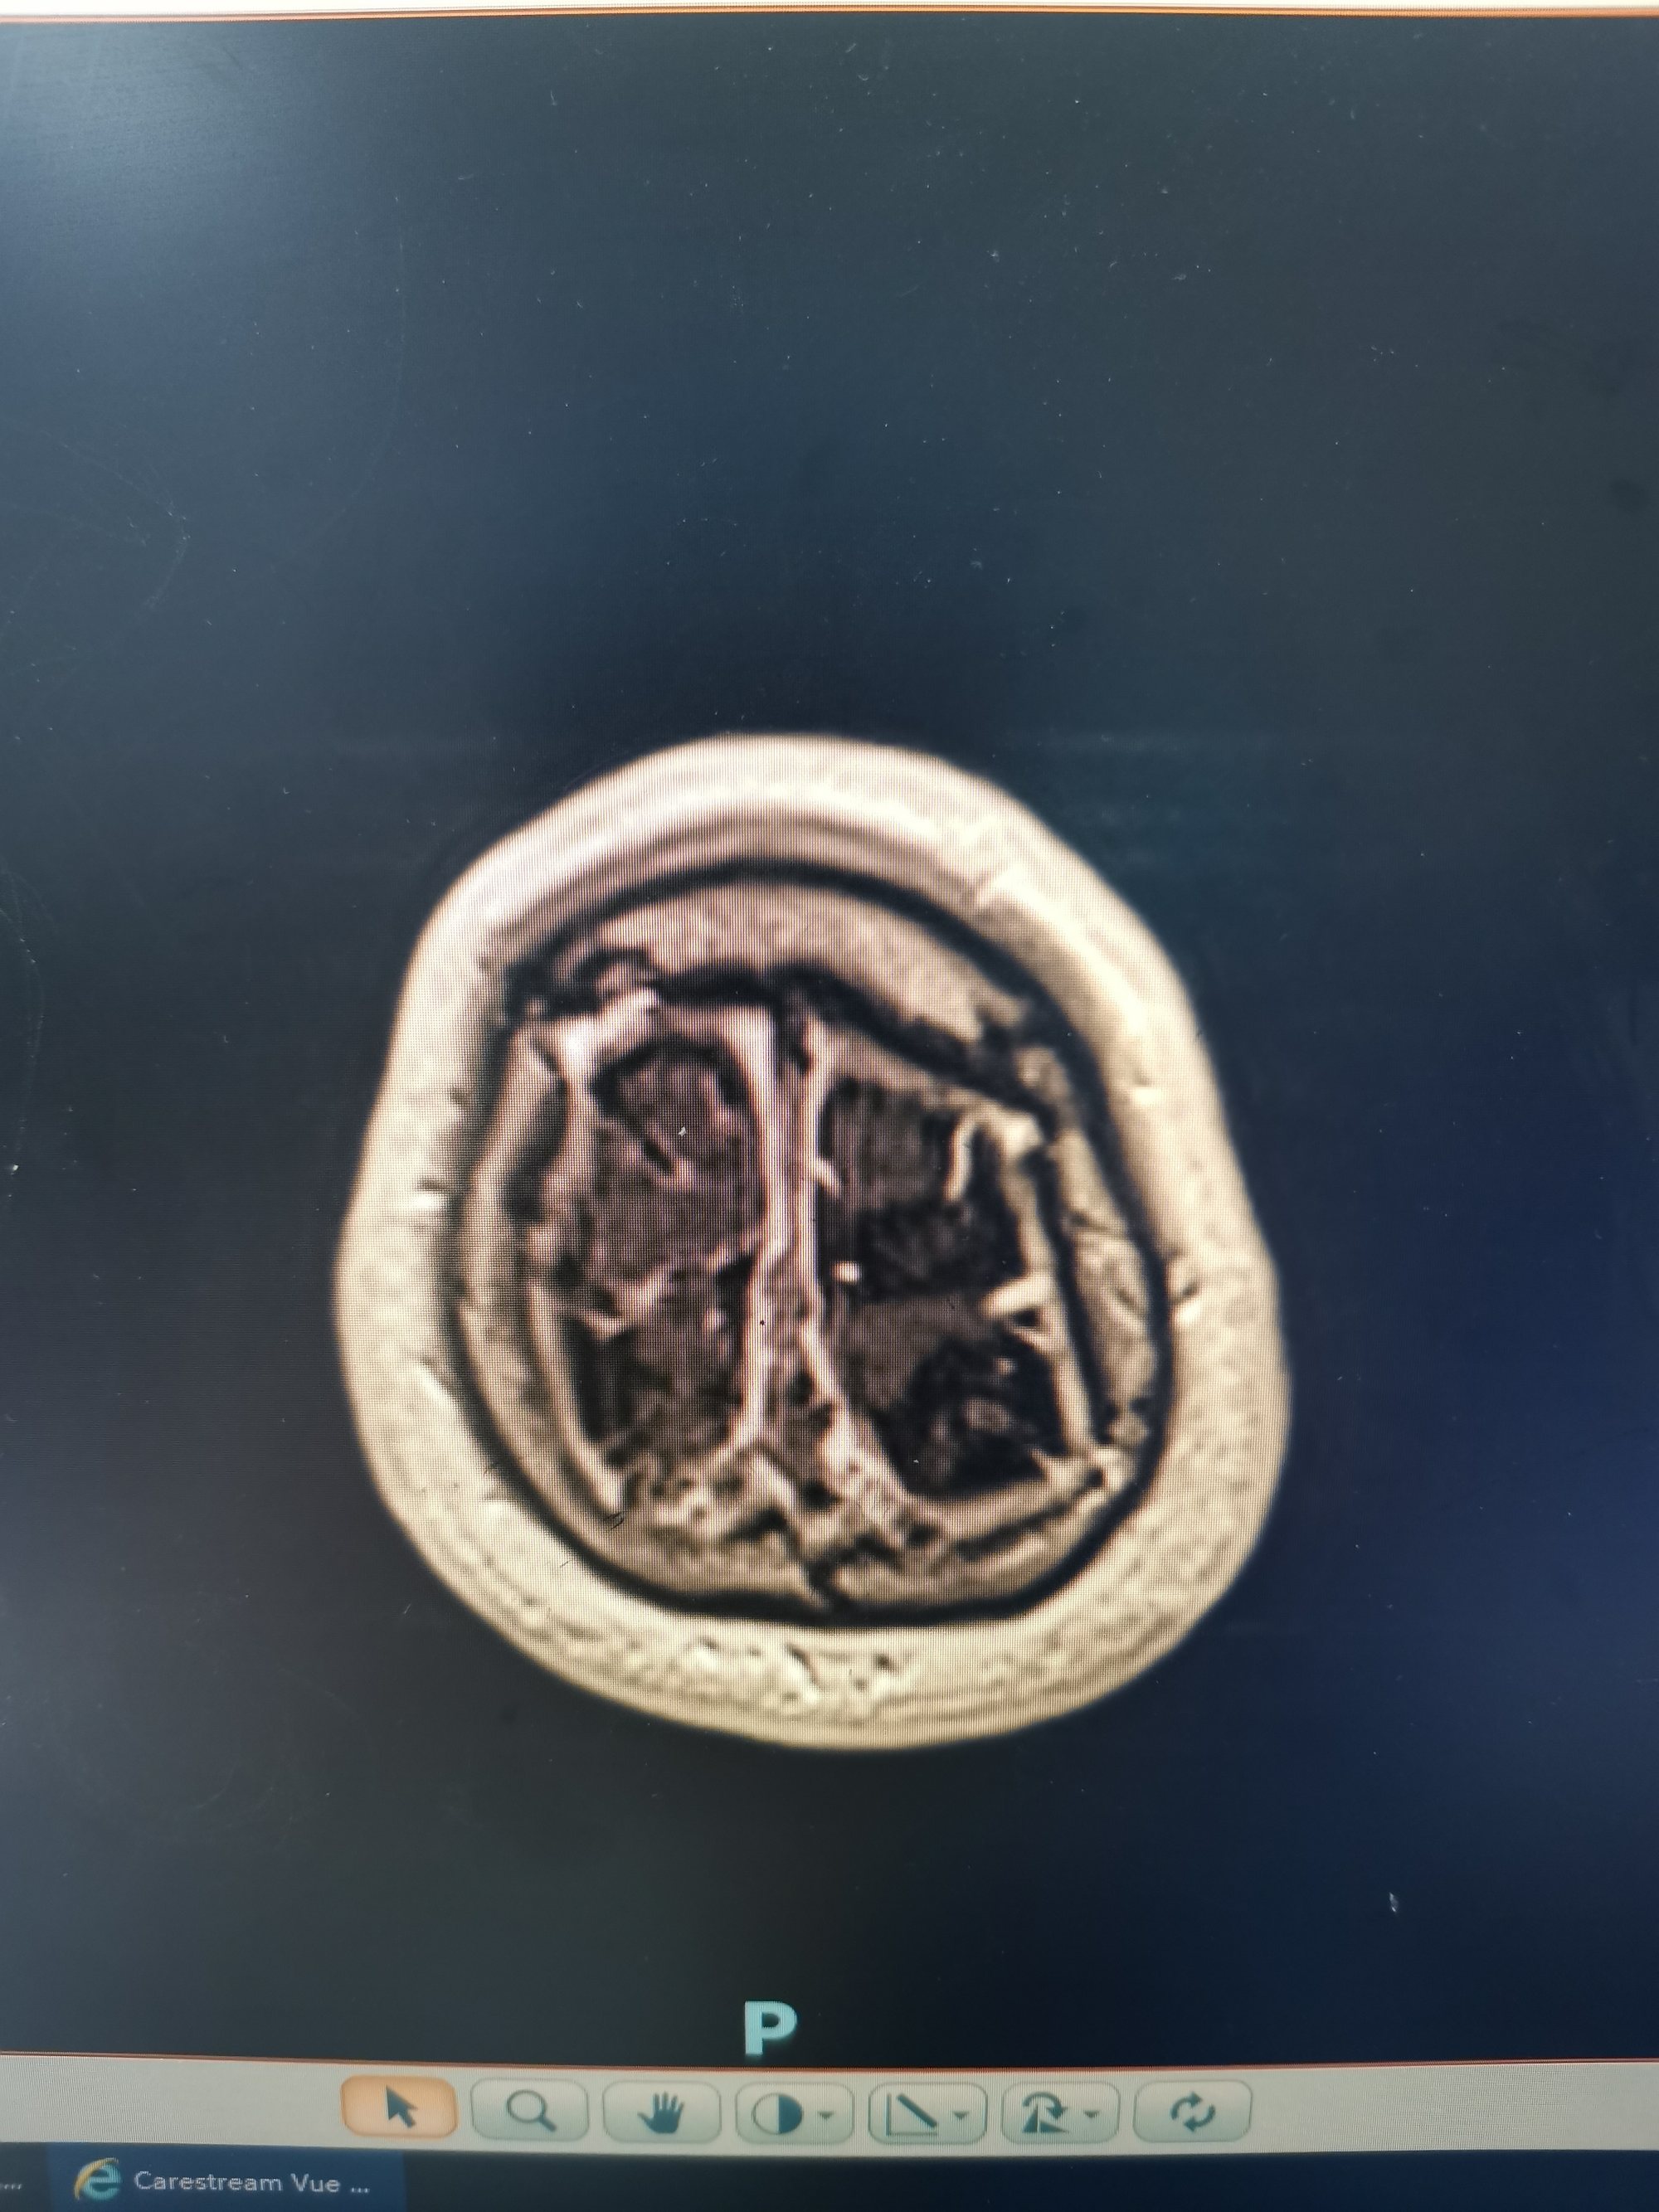

患者左侧横窦优势,左侧颈内动脉造影侧位见矢状窦起始部至横窦水平未显影。

微导管微导丝经颈静脉入路将中间抽吸导管带入矢状窦。

抽吸导管上行过程中在横窦部位上行困难,抽吸无法抽出血栓。微导管在微导丝引导下到达矢状窦起始部位微导管造影见矢状窦起始部位血栓影,血流无法经矢状窦回流,经额极静脉逆向经颅底向颅外段静脉引流。

在矢状窦起始部释放取栓支架锚定后将中间导管带入支架近端。

中间导管到位后冒烟确定血栓位置。